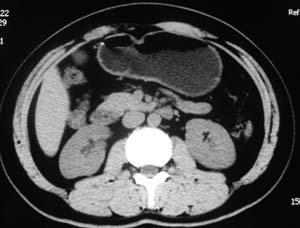

以下是引用子期在2010-3-19 20:47:00的发言:[br]血管畸形的ct增强应该有明显强化,本例并不相符合。本例双肾局部的略低密度影,累及肾盂,局部皮质明显变薄、内陷,增强扫描有轻度的强化,应考虑为炎性病变,患者为年轻男性,累及双肾的感染以结核较常见,可以没有明显的临床症状,尿中有时候也并不能查出什么;肾脓肿常有明显感染中毒症状,本例不符,另外一般的肾盂肾炎或肾小球肾炎通过小便就可确诊,其它还不能排除的是黄色肉芽肿性肾盂肾炎,然而单凭ct一般也很难鉴别。